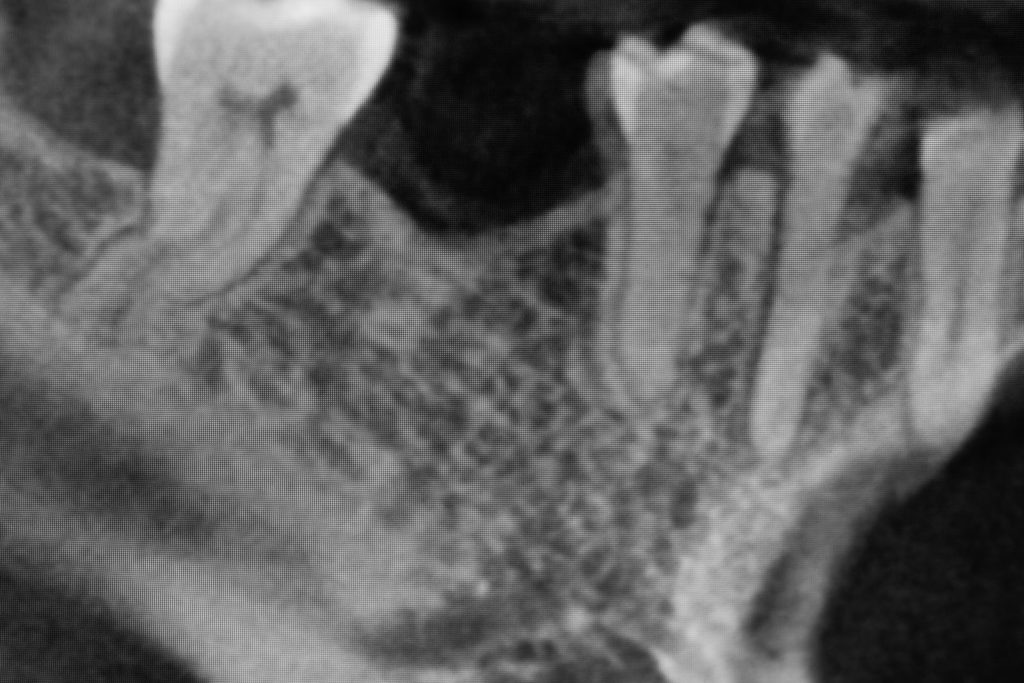

Przed podjęciem leczenia należy określić stopień zaniku kości szczęk oraz żuchwy. W tym celu przeprowadza się badanie kliniczne oraz odpowiednią diagnostykę obrazową pacjenta. Uwzględnia ona zdjęcie panoramiczne OPG jako podstawę dwuwymiarowego obrazowania podłoża kostnego oraz możliwe jest badanie tomograficzne CT lub bardziej precyzyjna tomografia stożkowa CBCT. Opcjonalnie wykorzystywana diagnostycznie tomografia pozwala na bardziej wnikliwą ocenę stopnia zaniku kości w trójwymiarowym, przestrzennym obrazie.

Precyzja projektu druku siatki bazuje na dokładności odwzorowania kształtu kości w stożkowej tomografii komputerowej CBCT, co zapewnia ich dobre przyleganie do podłoża kostnego oraz ogranicza powstawanie powikłań w postaci obnażania się siatek.